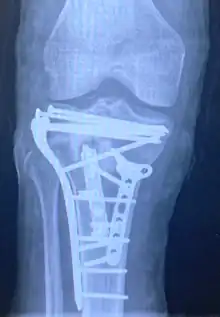

Treatment

Pain may be managed with NSAIDs, opioids, and splinting.[1][2] In those who are otherwise healthy, treatment is generally by surgery.[1] Occasionally, if the bones are well aligned and the ligaments of the knee are intact, people may be treated without surgery.[2] The surgery usually involves reducing the fractured fragments of the tibia plateau to their anatomical position and fixing them in place with screws only or fixed angle anatomical plates ensuring absolute stability. Implant selection is based on the type of injury. Generally, simple or incomplete fractures (Schatzker type 1) of the plateau are compressed with 6.5mm partially threaded cancellous screws. Complex type fractures will require a plate for enhanced stability. As the tibia condyles articulate with the femur (thigh bone) to form knee joint, any incongruity in the articular surface is unacceptable as it leads to early arthritis. Prolonged immobilization of the knee joint is also not recommended which result in stiffness of the joint and difficult recovery. It's currently debated what role primary total knee arthroplasty (Joint Prosthesis) plays in the treatment of tibial plateau fractures. Although accompanied with risks small studies have shown promising results.[9]